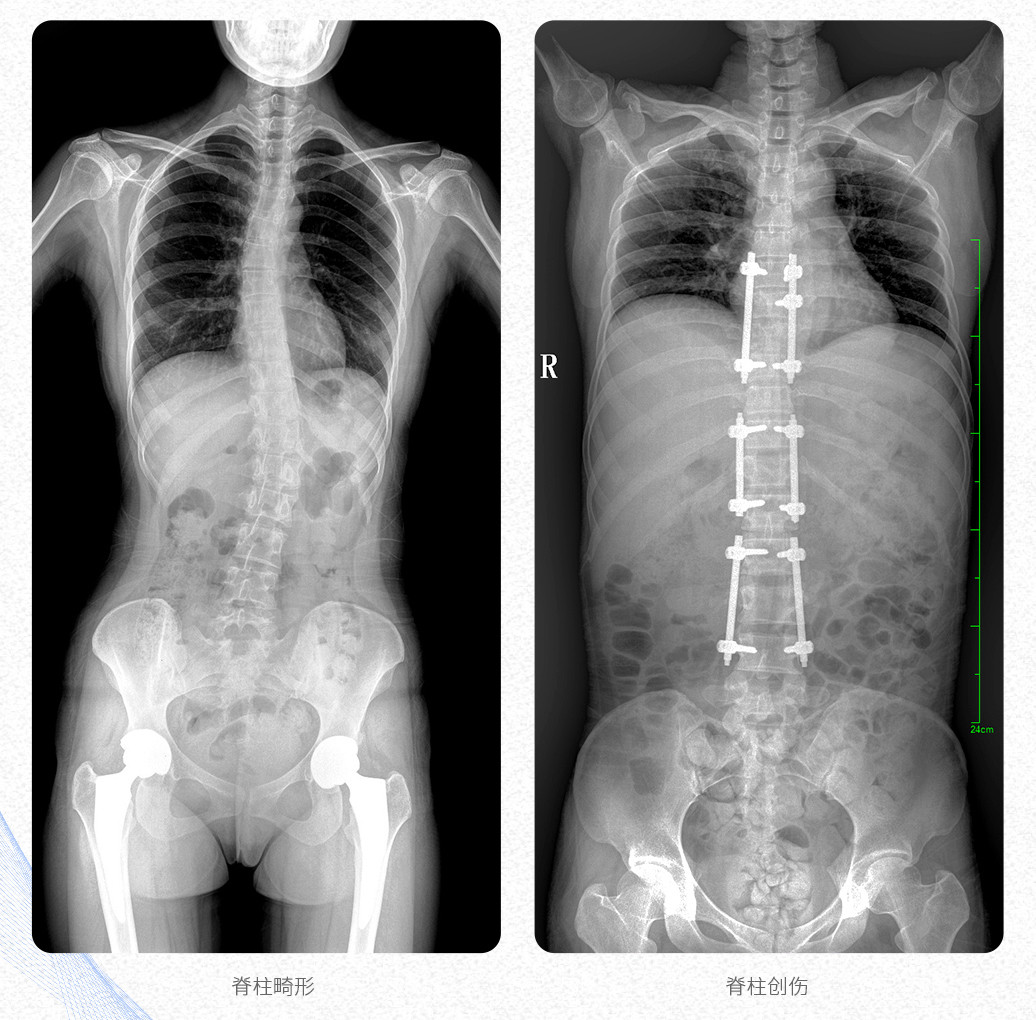

這款大視野U形臂DR的PLX8600數(shù)字化醫(yī)用X射線攝影系統(tǒng)主要應(yīng)用于骨科、創(chuàng)傷科、脊柱正畸科、放射介入科等科室;可供各級(jí)醫(yī)院支持全脊柱攝影、雙下肢攝影、脊髓造影、復(fù)雜創(chuàng)傷、人工關(guān)節(jié)置換、關(guān)節(jié)損傷的修復(fù)重建等大視野臨床應(yīng)用。

這款PLX8600數(shù)字化DR采用17"*34"有效視野,一次成像不拼接。相較于多張攝影再軟件拼接的DR設(shè)備,PLX8600動(dòng)態(tài)平板DR解決了拼接圖像存在密度不均勻,拼接處圖像配準(zhǔn)和放大效應(yīng)等問題,給臨床帶來了真正的大視野影像解決方案,高清畫質(zhì),準(zhǔn)確成像不失真,可一次性覆蓋全脊柱或雙下肢影像。

【產(chǎn)品臨床圖片】